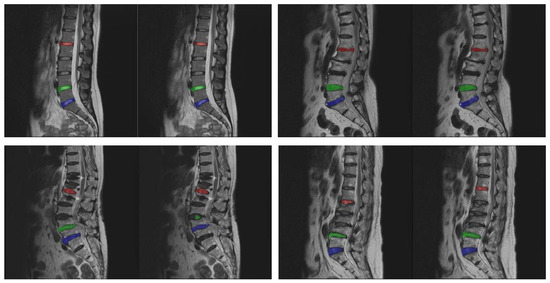

The number of experimental images is calculated based on the sample size estimated by the confidence interval [31]. If a 95% confidence interval is set and a standard deviation of 0.01 and a margin of error of 0.04% are used, then the most conservative sample size can be calculated, which is approximately 2400 images. The number of collected images, about 3000 images, exceeded the most conservative sample size required. The experimental images were randomly divided into a training set and a test set, which are 2674 and 308 images, respectively. Figure 1 shows some experimental image samples and corresponding manually labeled standard masks.

Figure 1. Experimental image samples and the corresponding manually labeled mask.